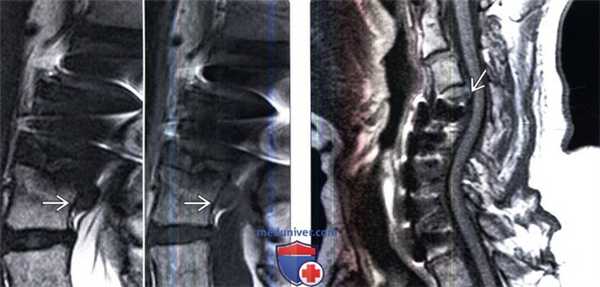

(Слева) Сагиттальная МР-томограмма в режиме Т1, пациент после вентрального спондилодеза СЗ-С5 с костной пластикой. Признаки дегенеративных изменений С5-С6 сегмента с развитием на этом уровне центрального стеноза позвоночника. Врожденный костный блок на уровне С6-С7 еще более увеличивает биомеханические перегрузки на уровне С5-С6 сегмента.

(Справа) Сагиттальная МР-томограмма этого же пациента в режиме Т2. На уровне С5-С6 видны признаки дегенерации и центрального стеноза с сужением субарахноидального пространства. Зона гиперинтенсивности паренхимы спинного мозга на уровне С5-С6 представляет собой очаг миеломаляции.